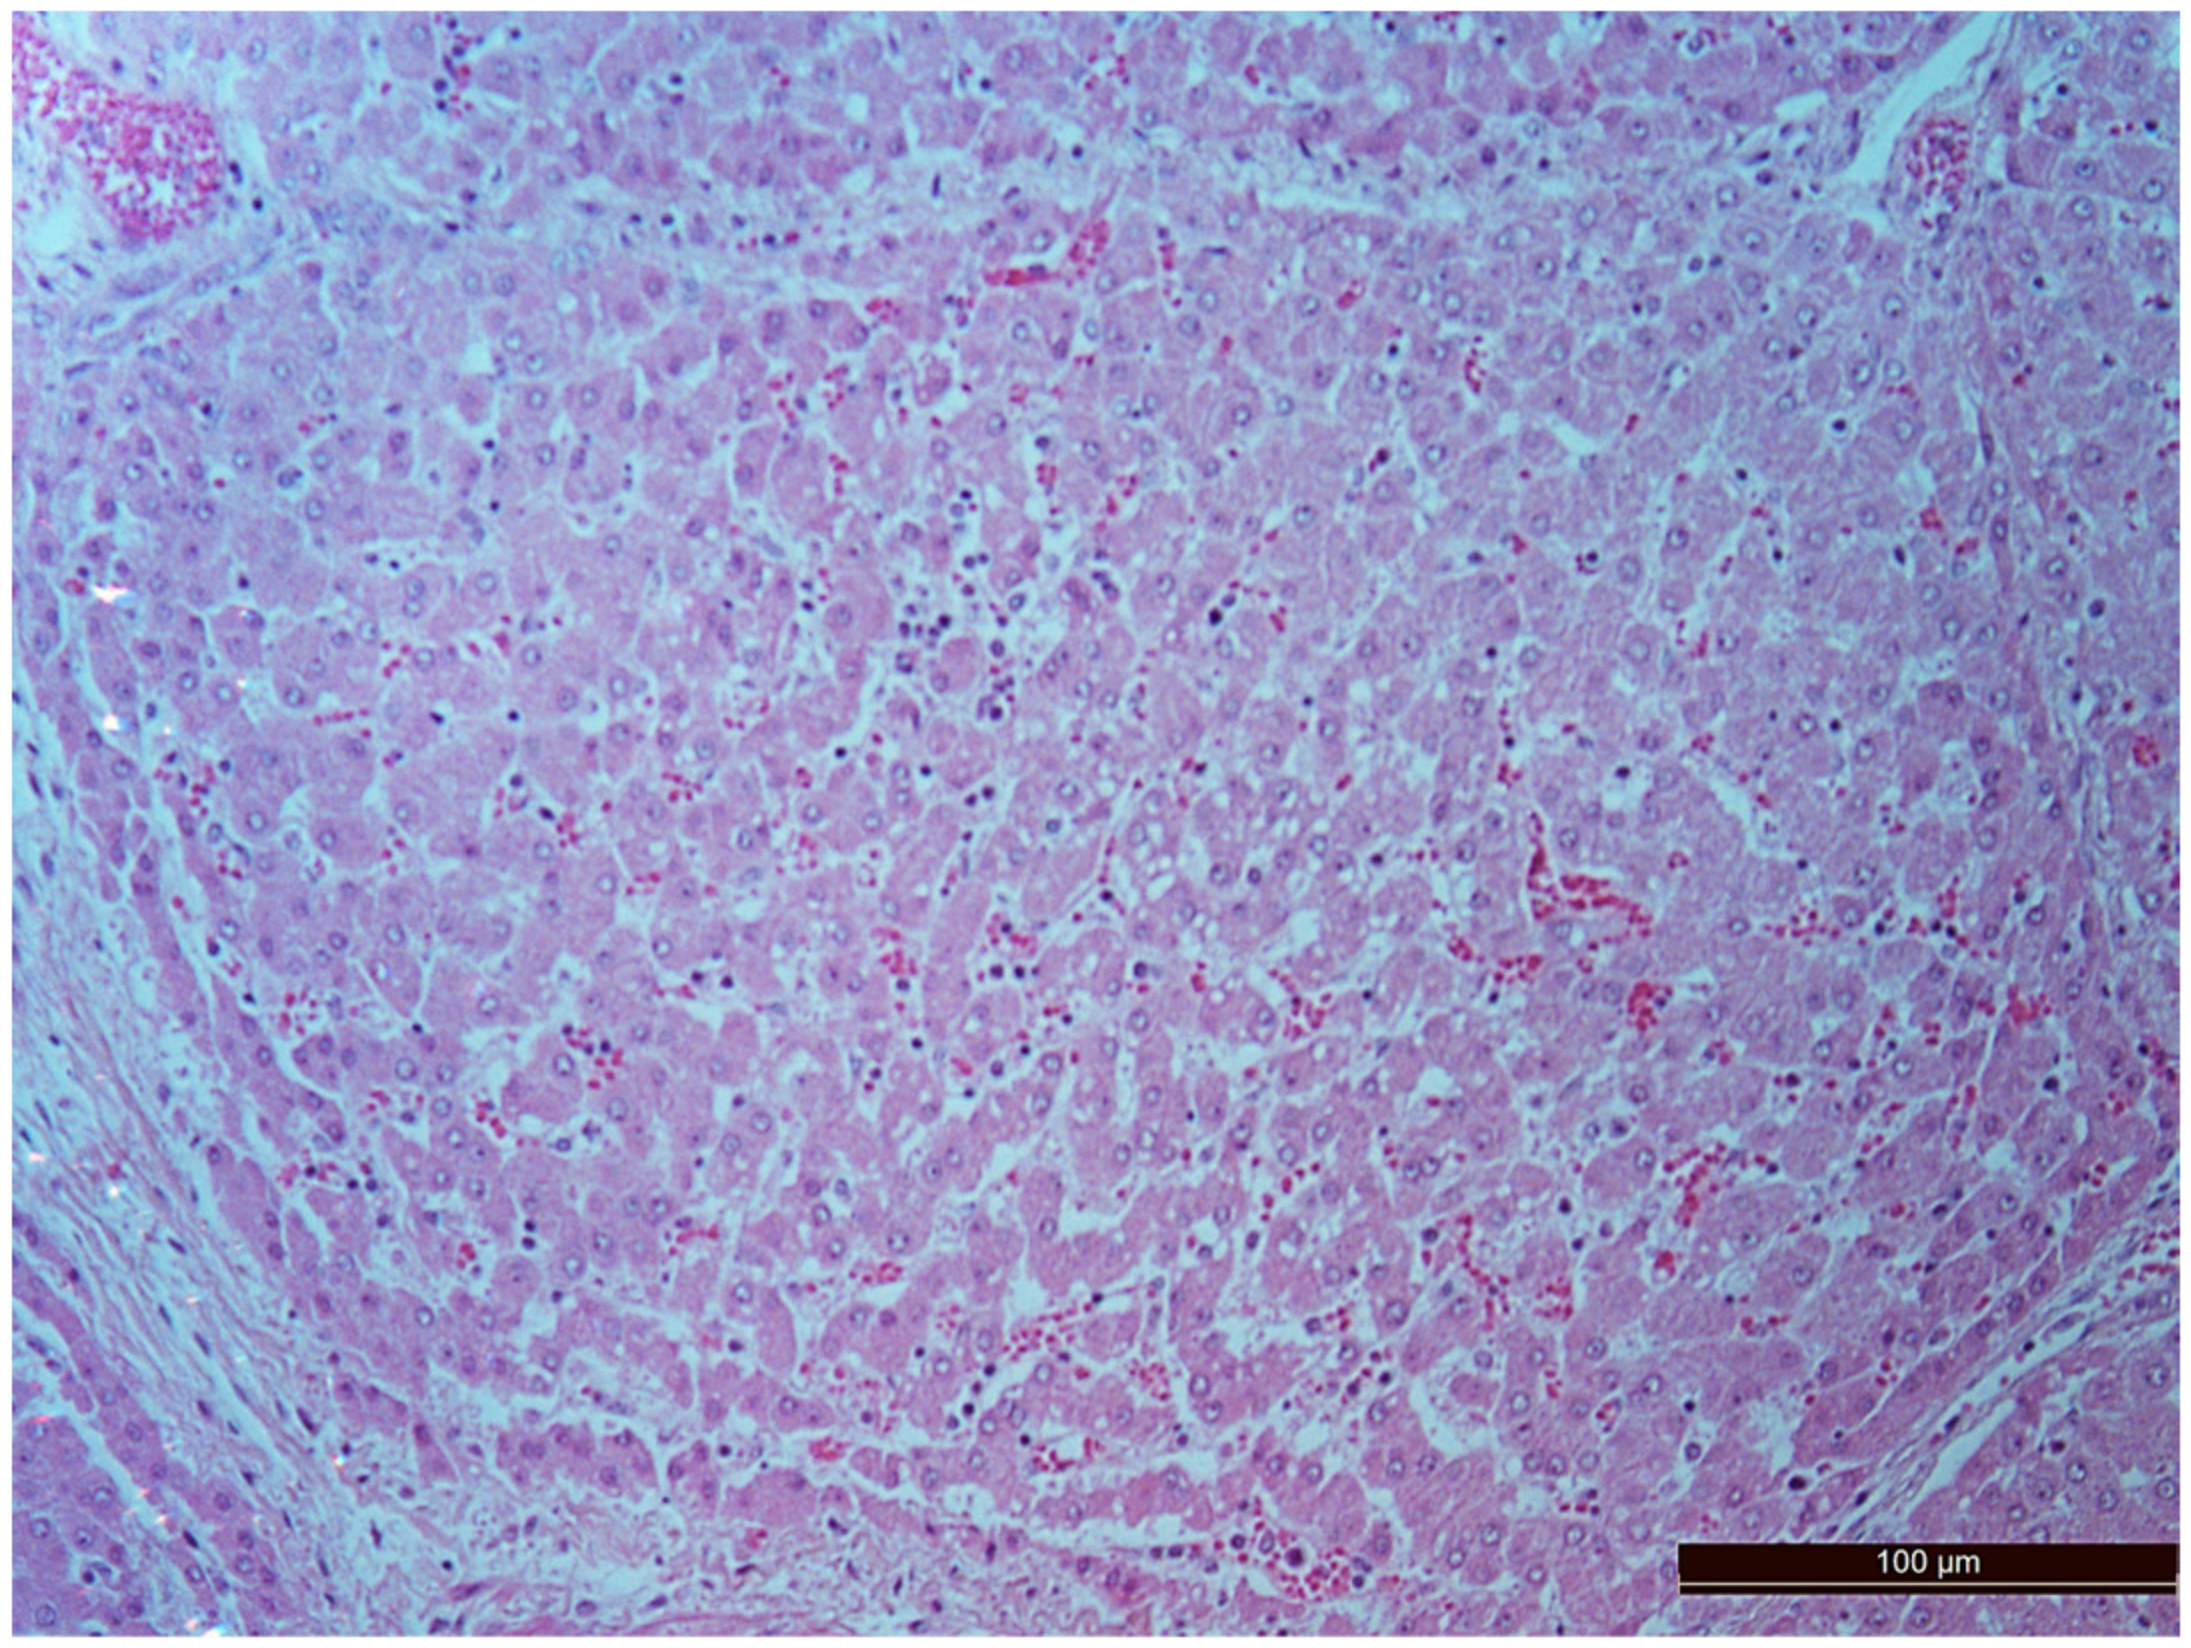

3.2. Pathology of the Liver